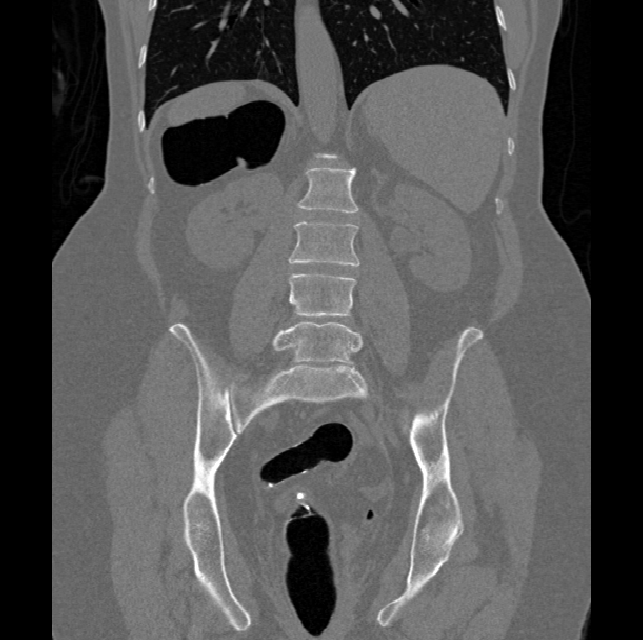

Spinal imaging via computed tomography (CT), magnetic resonance imaging (MRI), radiography, ultrasound, positron emission tomography (PET), and other radiologic imaging modalities is essential for noninvasively visualizing and assessing spinal pathology. Computational methods support and enhance a physician’s ability to utilize these imaging techniques for diagnosis, noninvasive treatment, and intervention in clinical practice. Analysis algorithms developed in the field of computer vision, computer graphics, signal processing, and machine learning have been adapted to analyze spinal images (Li et al., 2015). Conventionally, CT is preferred to study the spine due to a high bone-soft tissue contrast. There are diverse image appearance variations due to differences in vertebral position, metal artifacts and spinal diseases, etc., challenging the analysis algorithms. Fig. 1 gives some examples of these various conditions.

We calculate the two metrics of each vertebra, and the results are reported in Table 2. On the one hand, our experimental results are close to those reported in reference (Sekuboyina et al., 2020) with the same model (nnUnet), verifying the high quality of our annotations. On the other hand, Table 2 shows it is difficult to segment the diseased vertebrae (the DSC of L6 is almost 0). Specifically, the existence of L6 confuses the model, resulting in prediction dislocations (see the last row in Fig. 4). Thus, our labeled dataset, which contains many L6 cases, is very valuable for the diseased vertebrae segmentation (we have stated those cases that are hard for annotation in the readme.txt file). Table 2 illustrates that the model trained with our annotations can achieve good performance on our CTSpine1K dataset but a much worse performance on the VerSe Challenge datasets, which explains there is an obvious domain gap between our annotated dataset and the public dataset. We infer the reason is that the COlONOG dataset is based on an empty stomach and colon, confusing the deep learning model by the changes of air content in the abdomen (see Fig. 3). Therefore, our annotations are a good complement to the existing datasets.